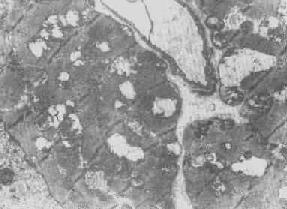

在由各种原因引起的细胞变性和坏死过程中,粗面内质网的池一般出现扩张,较轻的和局限性的扩张只有在电镜下才能窥见,重度扩张时则在光学显微镜下可表现为空泡形成,电镜下有时可见其中含有中等电子密度的絮状物。在较强的扩张时,粗面内质网同时互相离散,膜上的颗粒呈不同程度的脱失。进而内质网本身可断裂成大小不等的片段和大小泡(图1-6)。这些改变大多见于细胞水肿时,故病变不仅见于内质网,也同时累及Golgi器、线粒体和胞浆基质,有时甚至还累及溶解体。

图1-6肝细胞粗面内质网扩张 ×24000